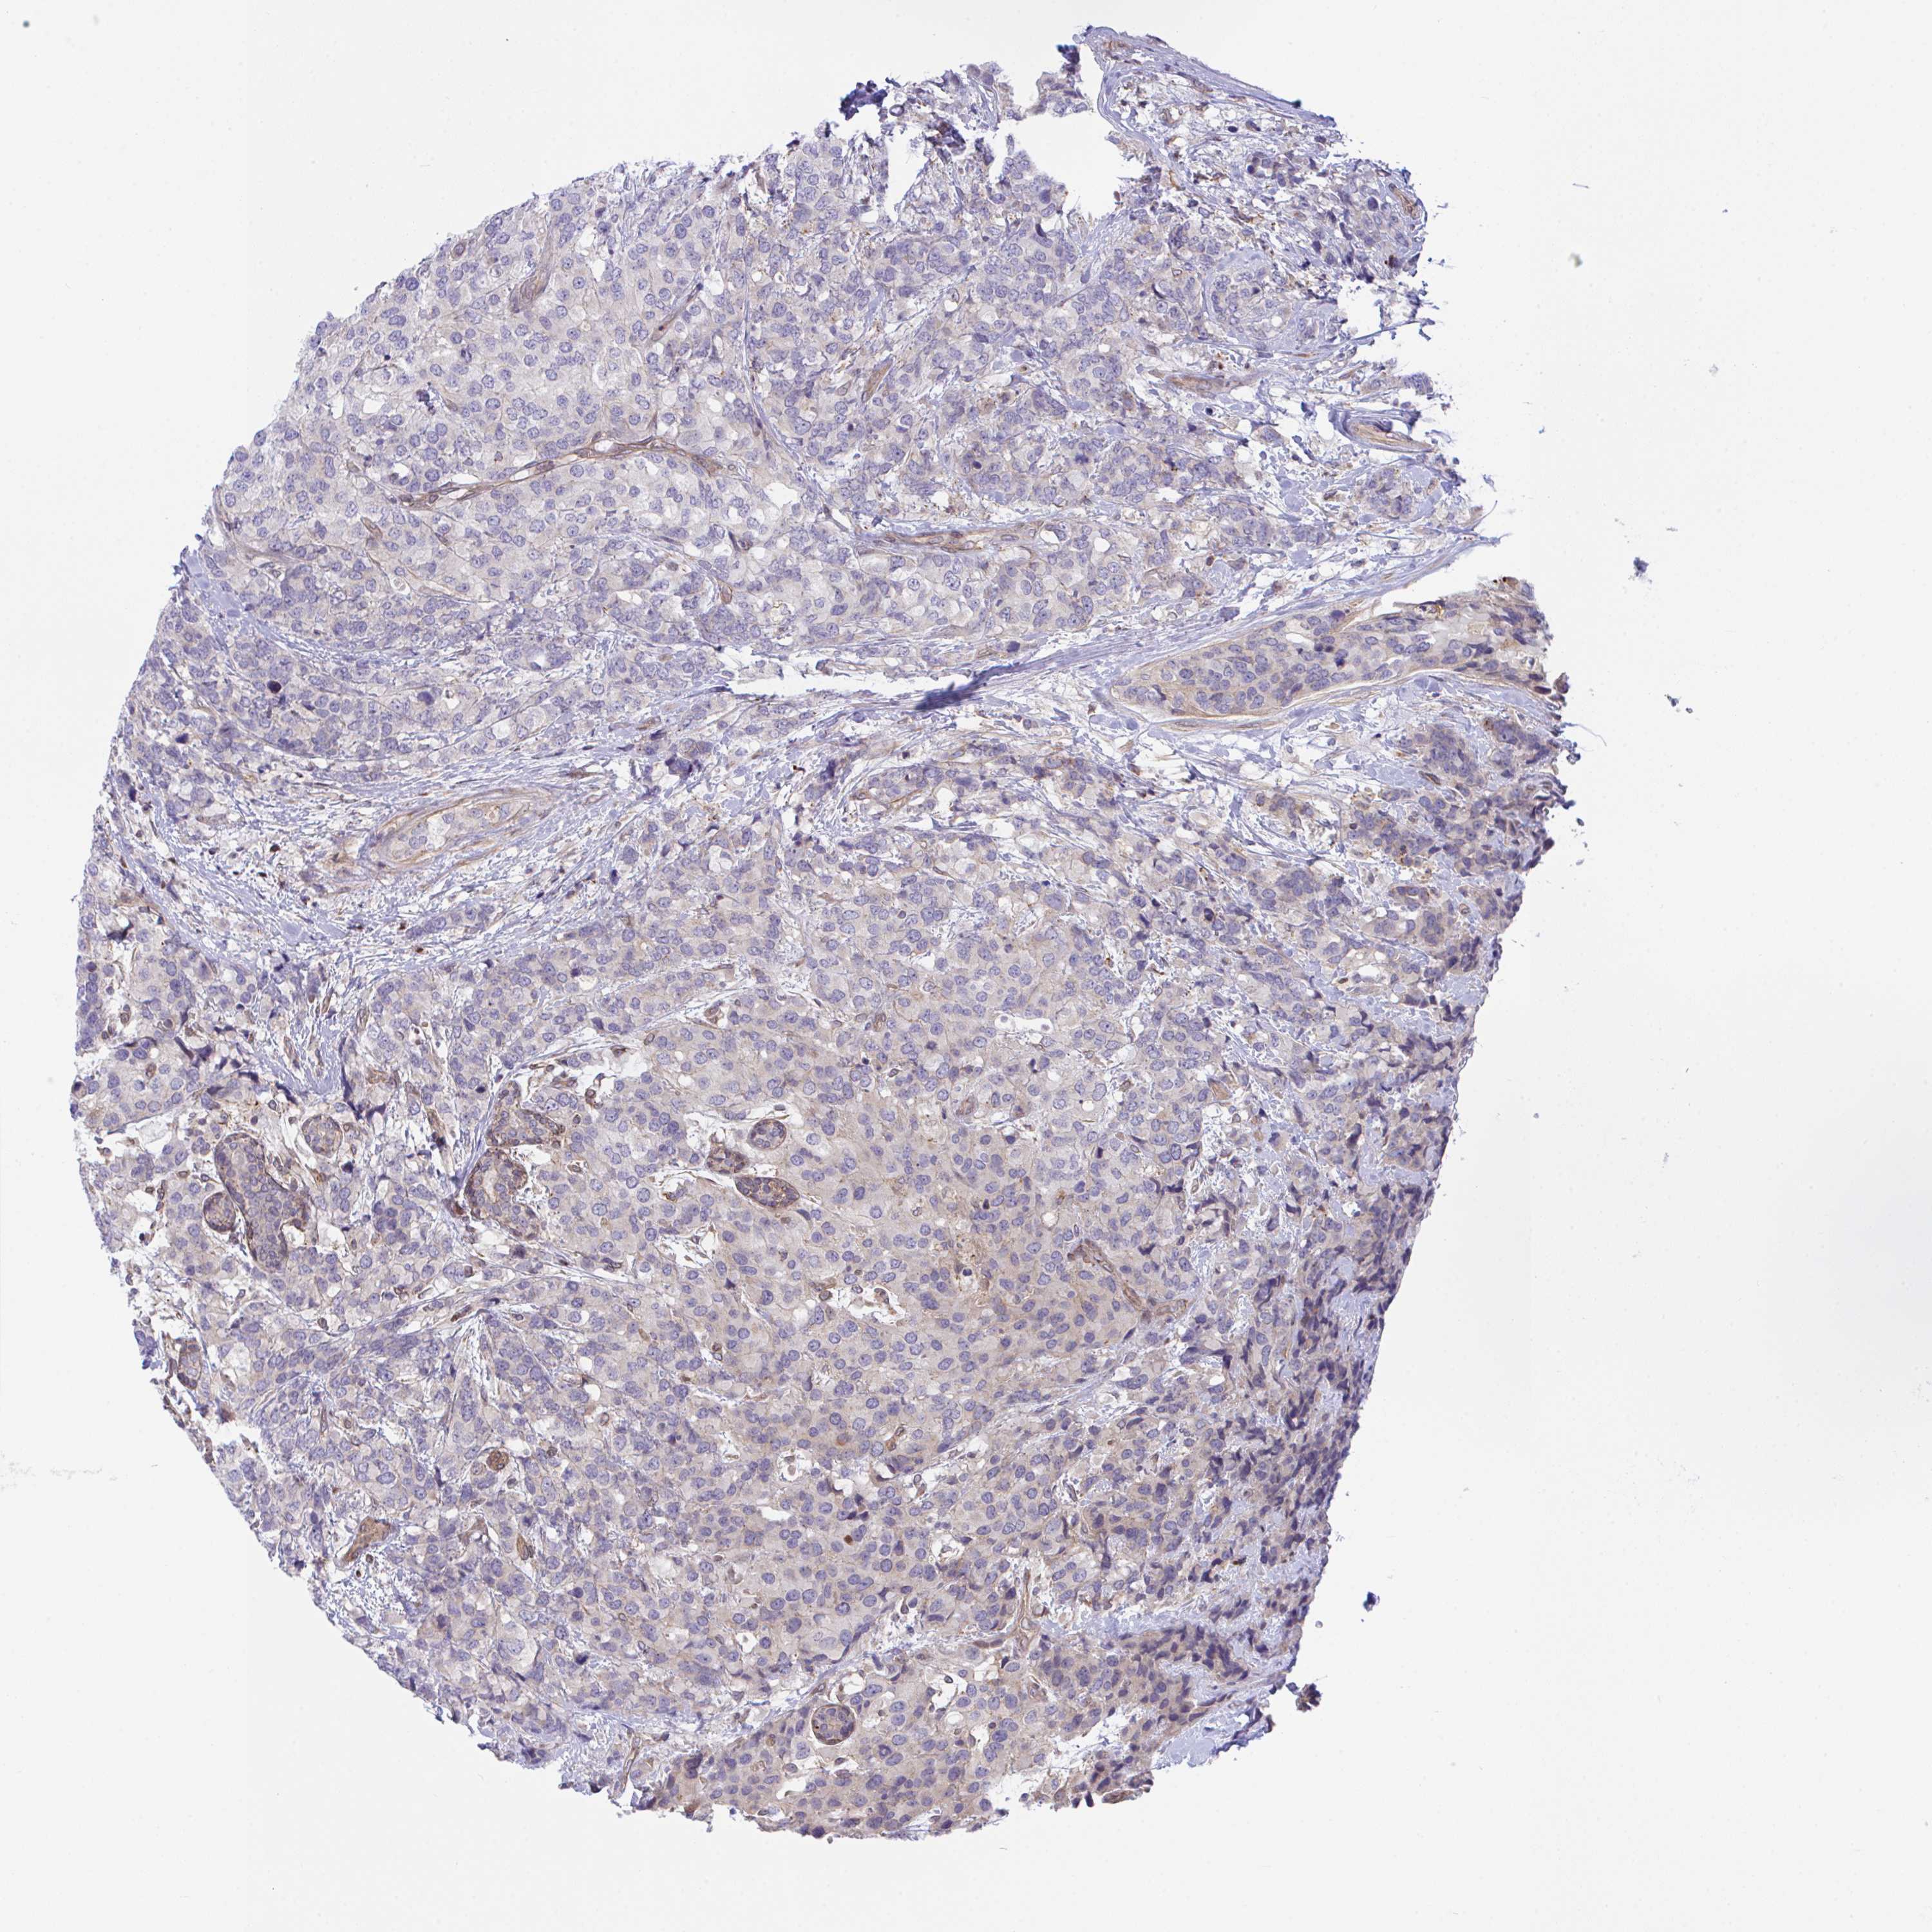

CANCER BREAST CANCER Show tissue menu

BRCA TCGA BRCA VALIDATION PROTEIN EXPRESSION